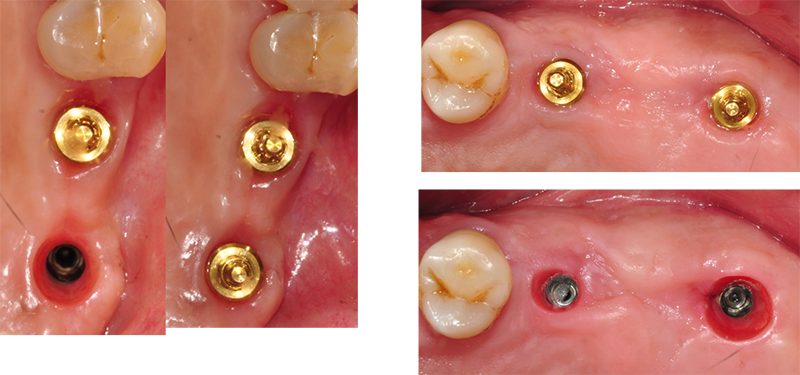

Healing Ab

1-piece

Ab

Convertible Ab(EZC,MUA,Octa µîµî)

2-piece Ab

À» ö°Å ÇßÀ» ¶§

ÀÕ¸ö ³»¸éÀÇ ¸ð½À.

Micro-gap or Micro mobility

»¡°²°Ô µÇ°Å³ª Çǰ¡ ³ª¸é ¾È µÈ´Ù.

Micro mobility°¡ ÀÖÀ¸¸é ¹ßÀûµÈ Ä¡ÀºÀ» º¼ ¼ö ÀÖ´Ù.

35N ÈûÀ¸·Î Á¶¿©Áø convertible abutmentÀ» Ç®¾î¼ »©º¸¸é ¾à°£ ÇϾé°Ô º¸ÀÌ´Â °æ¿ìµµ

ÀÖ´Ù. ±×¸®°í »ì¦ Âõ¾îÁö¸é¼ Ç͹æ¿ïÀÌ ¸ÎÈ÷´Â

¾ç»óµµ º¸ÀδÙ. Hemi-desmosome¿¡ ÀÇÇÑ ºÎÂøÀÌ ¶³¾îÁö¸é¼ ³ªÅ¸³ª´Â °á°ú´Ù.

Hemi-desmosome¿¡ ÀÇÇÑ ºÎÂøÀÌ ¼Õ»ó ¹ÞÁö ¾Ê¾Æ¾ß ÀÕ¸ö ÇϹ濡 ÀÖ´Â Ä¡Á¶°ñµµ º¸È£°¡ µÈ´Ù. Àý´ëÀû ¸íÁ¦·Î ¿©±â´Â °ÍÀÌ ÁÁ´Ù.